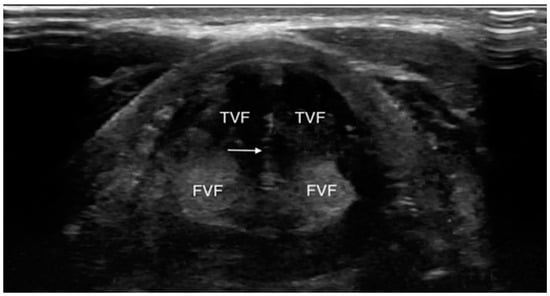

4.1.3. Laryngeal Edema Assessment Pre-Extubation

4.2. B: US and Breathing